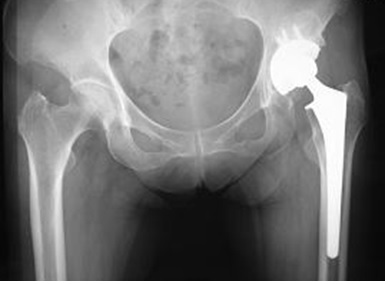

変形性股関節症 股関節の軟骨がすり減って関節が変形しますと、痛みにより歩行が困難となり日常生活に支障が生じます。人工股関節置換術は、術後の脱臼の危険性も少なく術後数日より離床、歩行が可能となります。